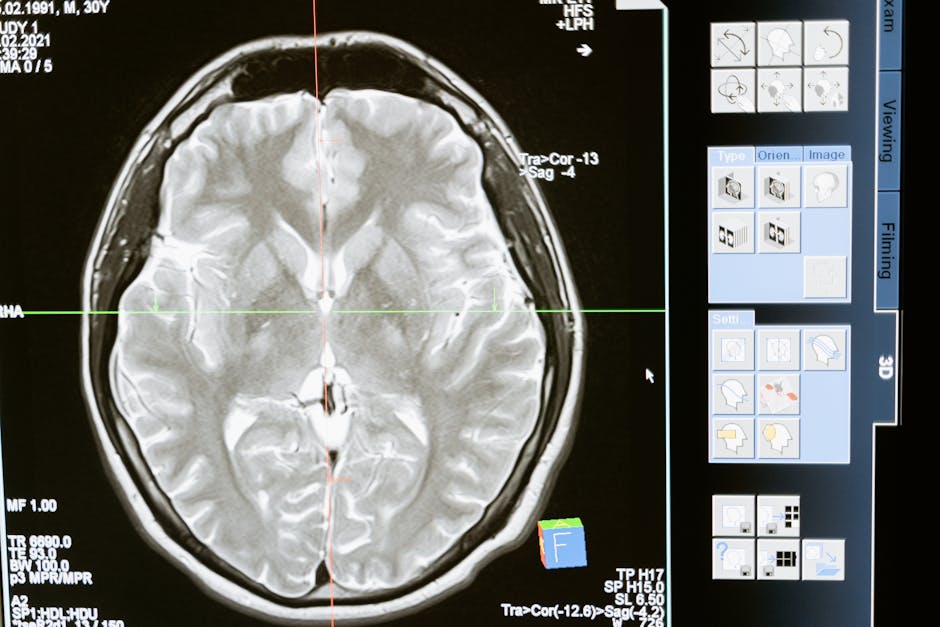

Traditional brain-computer interfaces often rely on implanted electrodes or scalp surface electrodes (EEG). Implanted electrode systems can yield high-fidelity signals but require surgery and carry infection, recovery, and long-term biocompatibility challenges. Noninvasive approaches typically trade signal fidelity for safety and accessibility.

Merge Labs claims its path will use molecular interfaces and deep-penetrating modalities such as ultrasound to transmit and receive information from neural tissue. If proven feasible at scale, those techniques could offer a middle ground: richer neural signals than standard EEG without the invasiveness of surgical implants.

- Signal specificity: Noninvasive sensors must isolate meaningful activity from noisy biological backgrounds.

- Resolution and latency: Many applications—especially real-time control—need high temporal and spatial resolution.